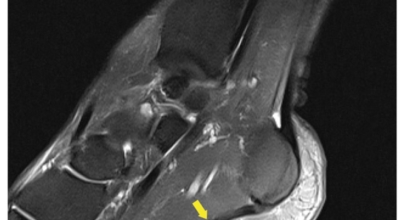

족저 근막이란 발가락 시작지점부터 발뒤꿈치뼈까지 발바닥 전체를 감싸고 있는 두꺼운 막을 말합니다. 족저 근막은 발바닥 아치를 지속시켜 발바닥이 지면을 내딛음으로써 발생하는 충격을 흡수하는 중요한 역할을 수행하고 있답니다. 이 족저 근막에 일차적으로 서서히 조직 손상이 일어나고 계속적인 활동으로 말미암아 염증이 커지면서 발 뒤꿈치 부근 통증을 일으키게 되는데 염증은 무리하고 반복적인 동작, 많은 사용으로 마찰에 의해 발생합니다.

족저 근막염은 염증에 의한 손상 및 통증을 유발하는 질환인데요 족저 근막염 증상은 일반적인 발뒤꿈치 통증 하글런드 병변의 기형으로 알려져 있으고 아킬레스 건과 관련이 깊다고 합니다. 특히 근육이 덜 풀린 아침 시간 대는 보행 시 날카롭고 바늘로 찌르는 듯한 심한 통증을 느끼게 된다고 합니다. 하지만 아침 시간 대를 지나 오후에 접어들면서 어느 정도 통증은 서서히 감소하기 시작한다고 하는데요 초기 증상이 나타난다면 꼭 전문의를 찾아 조기치료하는 것이 바람직합니다.